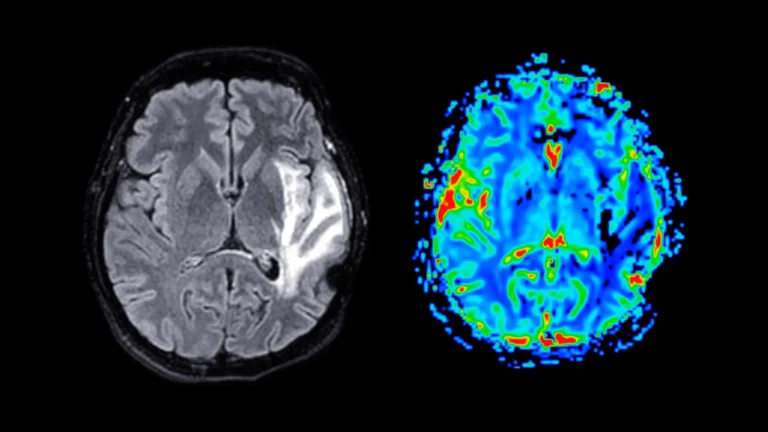

A groundbreaking artificial intelligence system developed at the University of Michigan is poised to revolutionize the interpretation...